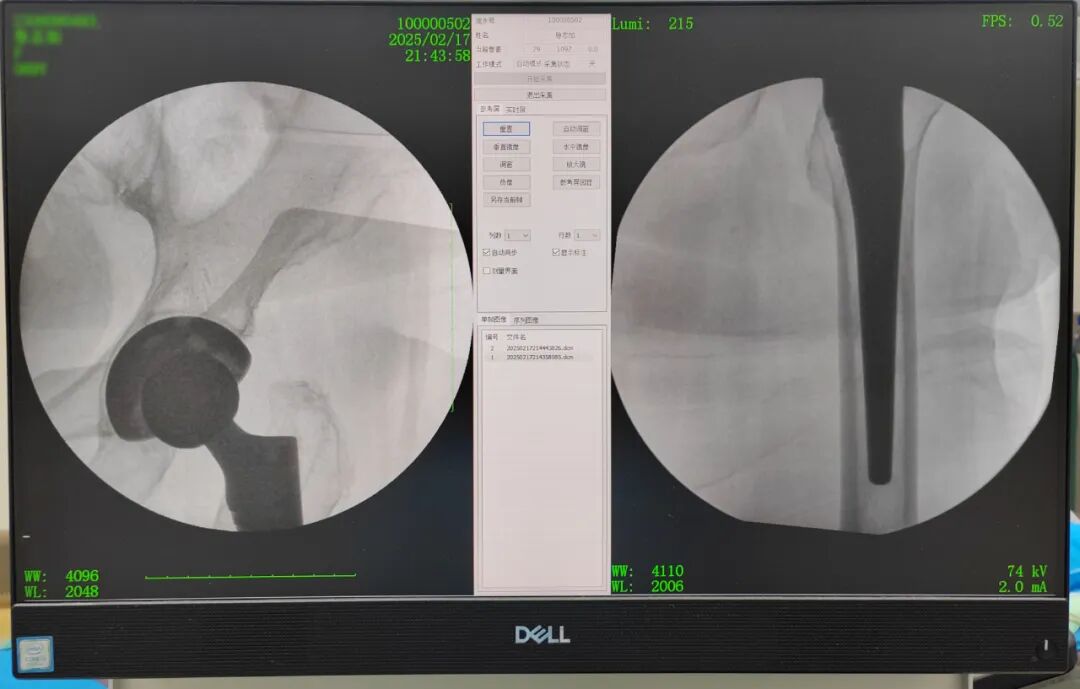

面对紧急情况,尽管做完相关检查后已是深夜,但我院医生和护士们却没有丝毫懈怠。立即启动了应急预案,在麻醉师的密切配合下,黄主任与彭主任凭借着丰富的经验和精湛的技术,仅用几分钟顺利完成复位。复位后复查DR影像显示复位效果良好,王阿姨疼痛消失,被送回病房进行持续观察和治疗。并对其再次进行了详细的术后指导,强调了人工关节置换术后的注意事项。

图片